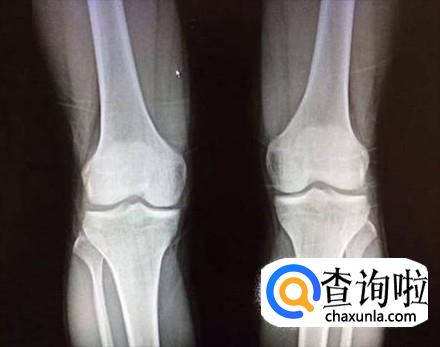

如果青少年的骨骼线没有闭合,那么通过一定运动是还可以在长高的,反之如果还想长高的话就只能通过手术了。